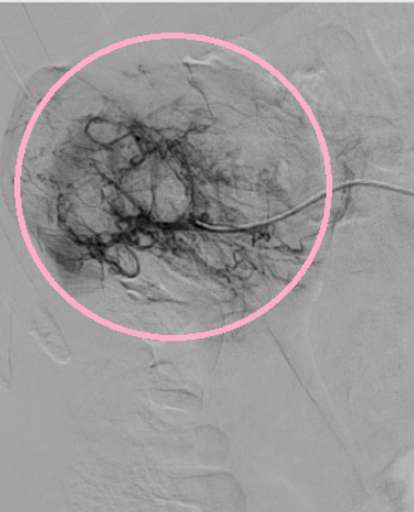

תמונות מההליך

שלבי הפעולה:

- הדגמת סלקטיבית של ה-AML בכליה הימנית. עושר של עורקים מפותלים ומורחבים (tortuous feeding vessels), היעדר מבנה קפילרי תקין, הסתעפויות לא סדירות מבנה זה מסביר את הנטייה לדימום ספונטני.

- במהלך האמבוליזציה – חסימה סלקטיבית של הענפים המזינים, אט אט פחות כלי דם נצפים.